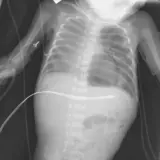

Over 2,100 interactive radiology cases, curated by radiologists for your level of training. Scroll, window, and view cases full screen โ€” just like on PACS. Click linked findings in each writeup to jump straight to them on the image. Cases include sample reports, a focused discussion section, original illustrations, and videos.

Casi completamente interattivi con gli strumenti che ti aspetti su un PACS: scroll, windowing, zoom, pan, misurazioni, ROI e modalitร  a schermo intero.

Annotazioni dettagliate evidenziano i reperti chiave direttamente sui casi. Clicca sui reperti collegati nella descrizione del caso per saltare alla loro esatta posizione sullo scan.